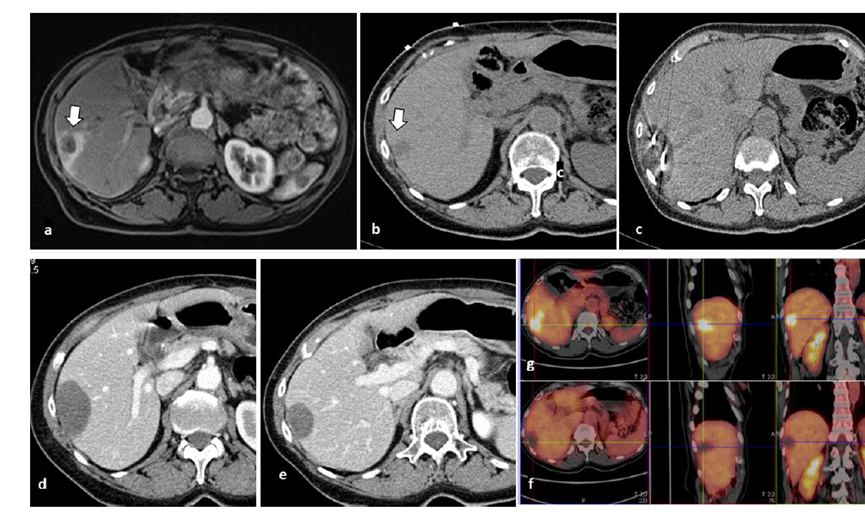

undefined

51歲男性患者,肝移植后復發(fā)病例

(a) 射頻消融后在病變邊緣顯示殘余增強。

(b) 冷凍消融術中影像顯示冰球完全覆蓋病變。

(c) 19個月后隨訪,沒有發(fā)生局部腫瘤進展。